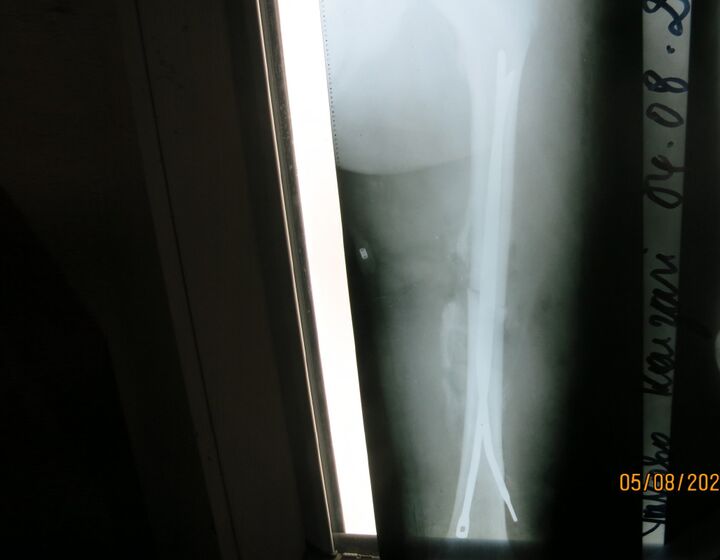

Es kommen spannende Fälle von Wachstumslenkung vor. Wie bei diesem Jungen, der zu Beginn der Behandlung fünf Jahre alt war. Der Beginn der Behandlung in so geringem Alter war notwendig, weil die Deformität so invalidisierend war, dass die Einschulung im folgenden Jahr wohl nicht möglich gewesen wäre.

Natürlich kommt auch viel Kinder-Traumatologie vor. Hier ist ein Beispiel von ECMES/ESIN eines Femurs mit Hilfe von Ender-Nägeln, die auch aus den Beständen der Tuttlinger Klinik stammen, die in Deutschland als nicht mehr als zeitgemäß gelten.